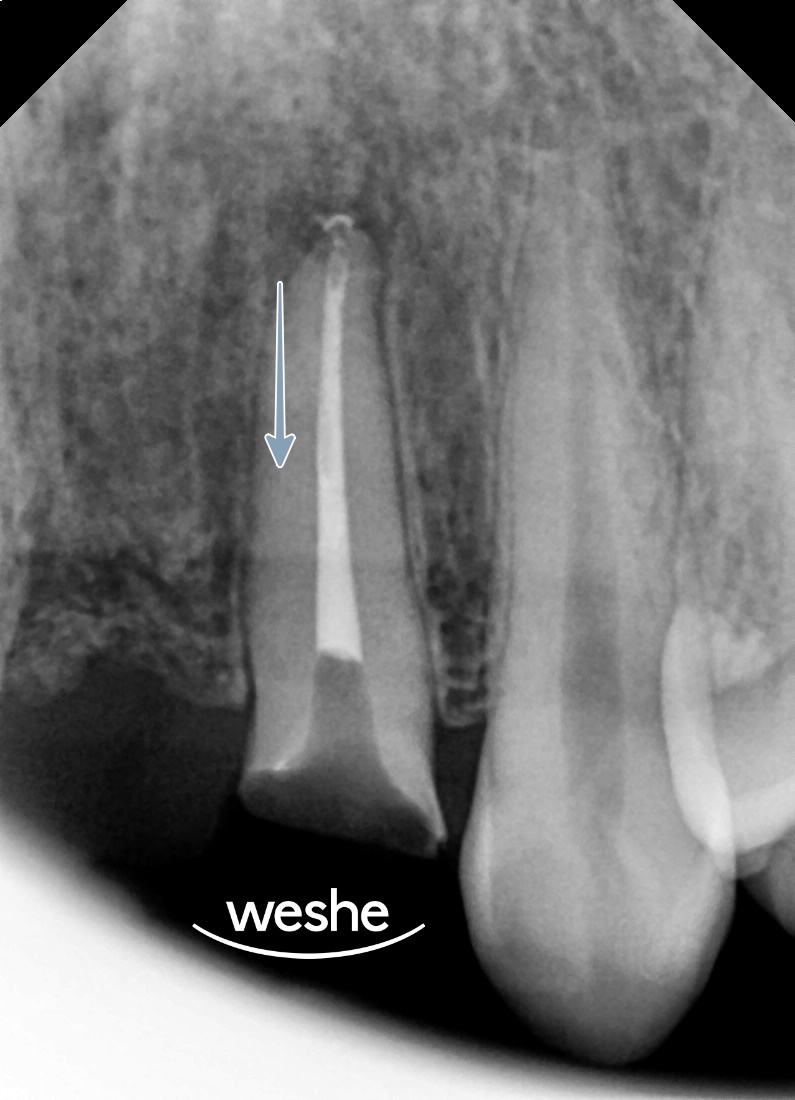

20250609

이동 속도는

치근 흡수나 치주 조직 손상을

유발할 수 있기 때문에

월 1mm 정도로 천천히 진행되는 것이 안전합니다.

과정은?

우선 22번의 근관치료를 진행합니다.

이전에 신경치료를 받은 치아지만

재감염이 발생한 경우가 많기 때문에

근관 내부를 다시 소독하고 충전합니다.

예시 사진

근관치료가 완료되면

교정적 정출을 위한 장치를 장착합니다.

교정 장치는 해당 치아에 브라켓을 부착하고

양쪽 인접 치아를 고정원으로 활용하여

수직 방향으로 견인력을 적용하는 방식입니다.

장치 장착 후 약 7주에 걸쳐

정기적인 내원을 통해 활성화를 진행합니다.

일반적으로 2-3주마다 내원하여

교정력을 조절하고 이동 정도를 확인합니다.

정출 과정에서는 치아가 위쪽으로 이동하면서

치은 조직도 함께 따라 올라옵니다.